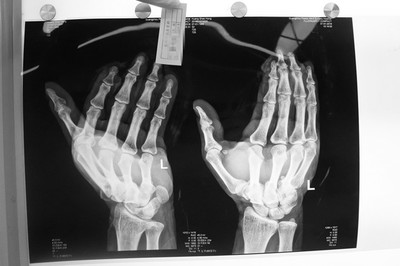

四肢创伤组织移植案例

右腹部旋髂浅动脉游离皮瓣移植

右臂皮瓣移植